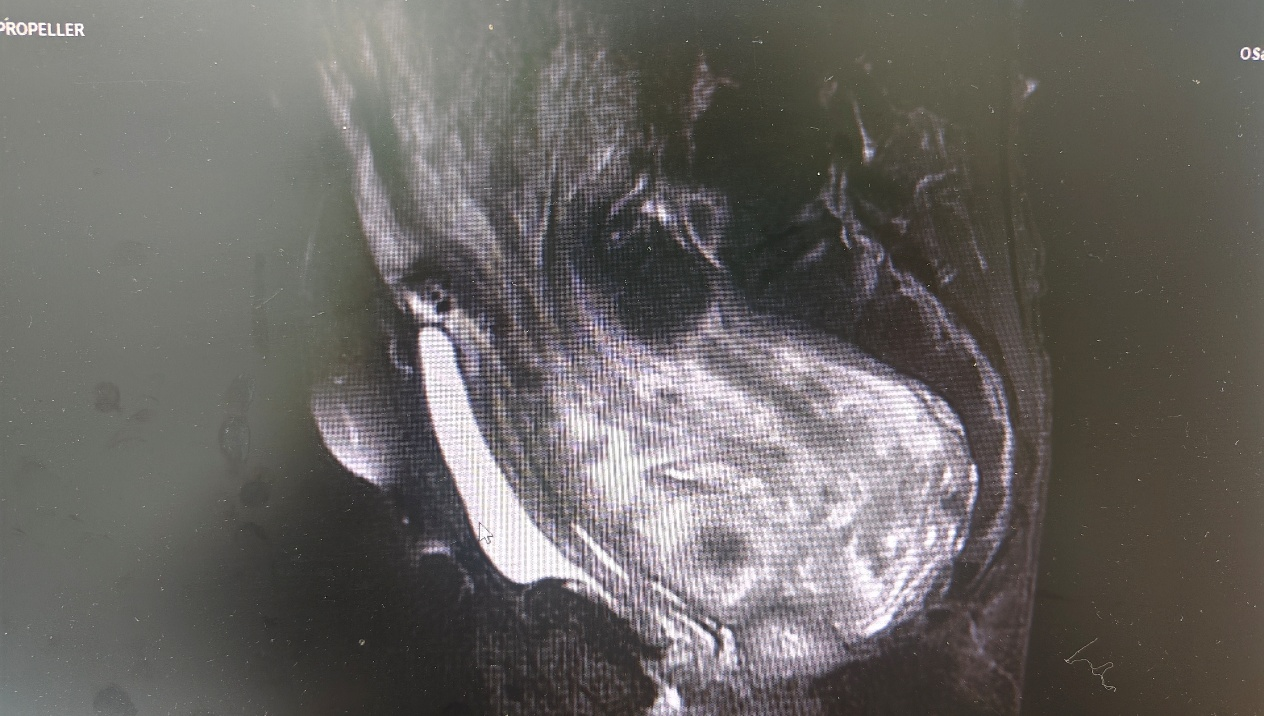

杨阿姨因盆腹腔巨大包块导致腹胀,并已严重压迫内脏,活动不便、呼吸不畅,少量进食即感腹胀加剧,于是来到靖州院区妇产科就诊。经副主任医师巫思红详细询问病史和细致体查,考虑该包块为良性实性肿瘤可能性大,需要尽快手术解除压迫、缓解不适。鉴于肿瘤体积巨大、血运极其丰富,周围解剖结构复杂,输尿管、髂血管等生命线密布其中,且杨阿姨已绝经,经与家属充分沟通并征得同意后,妇产科团队制定了周密方案,决定为杨阿姨施行全子宫切除+双附件切除+盆腹腔巨大肿瘤切除术。

手术由妇产科主任、主任医师向红云,副主任、副主任医师巫思红带领团队实施,术中探查发现难度远超预期:肿瘤为右侧阔韧带巨大肌瘤,自后腹膜占据了整个盆腹腔,右侧输尿管紧贴肿瘤内下方走行,分离过程稍有不慎,就可能损伤输尿管,导致术后尿瘘甚至肾切除,手术如同“雷区排雷”。手术团队沉着冷静,凭借丰富的解剖经验和精湛的技术,化身“拆弹专家”,在重重包围中仔细分离瘤体与输尿管的粘连,将输尿管完整地“骨骼化”游离开来,再逐一结扎供应肌瘤的粗大血管。经过近2小时的精细操作,这个重达6.59公斤(约13斤)的巨大包块连同全子宫及双附件被完整切除,术中出血极少,右侧输尿管毫发无损。术中快速病理报告证实为良性阔韧带肌瘤,这让所有医护人员和杨阿姨家属都长舒了一口气。